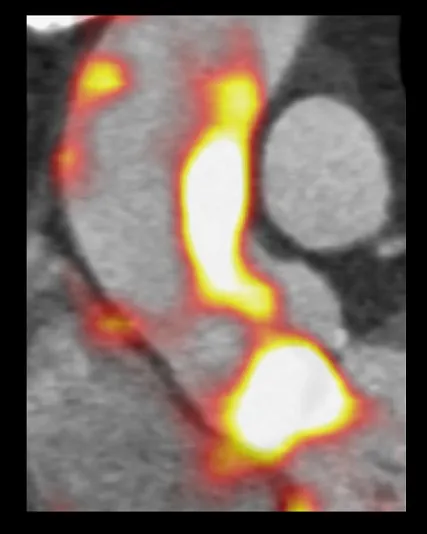

Can a new imaging approach help identify when patients with a bicuspid valve require surgery and thus save lives? Project title: Assessment of Risk in Thoracic Aortopathy using 18F-Sodium Fluoride: the AoRTAS study Funded: The British Heart Foundation Dr Niki Walker (lead researcher), Golden Jubilee National Hospital, Glasgow Image Prof David Newby, University of Edinburgh The aortic valve is a one-way valve between the heart and the aorta, the main artery from the heart that distributes oxygen-rich blood to the body. Normally, the aortic valve has three small cusps or leaflets (tricuspid valve) that open widely and close securely to regulate blood flow, allowing blood to flow from the heart to the aorta and preventing blood from flowing backwards into the heart. However, approximately 1 in 100 people, only have two small cusps or leaflets (bicuspid valve) instead of having three valves. For those with bicuspid valves, there is an increased likelihood of people developing heart disease in later life. For example, the aorta may become weak, meaning it can swell, tear or even burst. This can happen in early adult life when the consequences are often fatal. Image Although bicuspid aortic valve disease is present at birth, it usually is not diagnosed until adulthood because the defective valve can function for years without causing symptoms. It is often picked up incidentally with a murmur and the person’s General Practitioner will refer them to specialists to have a heart scan to evaluate the heart, valves and aorta. Currently, these patients remain under the care of their specialist, to have annual checks to try and assess if or when they will require surgical treatment to repair or replace the valve and part of the aorta, usually when they are in their 40s or 50s. This collaborative research between Glasgow and Edinburgh will test a new imaging approach, using 18F-sodium fluoride PET-MR, which highlights damaged parts of the aorta to assess whether this new imaging test can help to identify those patients who are at higher risk of such complications. Patients will be scanned at the Edinburgh Imaging Facility QMRI, using the Siemens Biograph mMR scanner. If successful, this technique could improve how we select which patients require surgery at certain times in order to prevent catastrophic complications of this condition. Projects details Grant amount: £343,823 Start date: 01 March 2019 Duration: 2.5 years No. of patients to be scanned: 100 Reference: BHF clinical research training fellowship FS/19/15/34155 Relevant links The British Heart Foundation Dr Niki Walker Professor David Newby Dr Alex Fletcher Edinburgh Imaging Facility QMRI Edinburgh Imaging equipment Heart / cardiovascular What is a PET-MR scan? Publication date 05 Mar, 2019